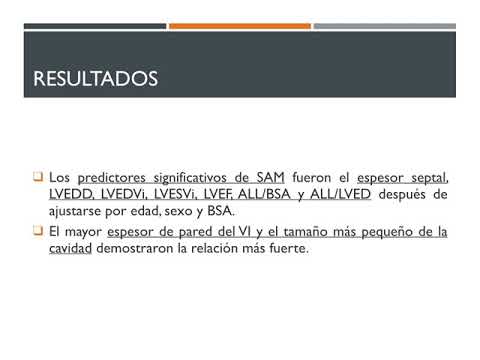

Ablación septal de miocardiopatía hipertrófica obstructiva. Dra. Sofia Gabriela Rodríguez. Residencia de Cardiología. Hospital C. Argerich. Buenos Aires

Alteraciones intrínsecas de la válvula mitral en mutaciones sarcoméricas de miocardiopatías hipertróficas. Dr. Gerardo Albarracín. Residencia de Cardiología. Hospital C. Argerich. Buenos Aires